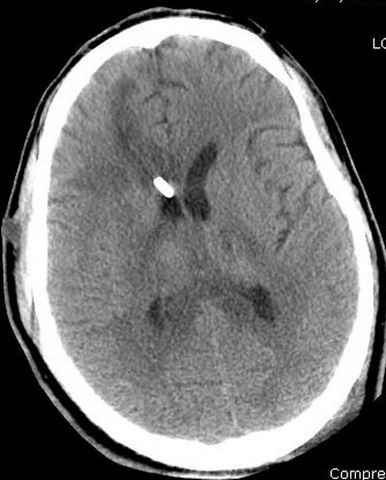

больному 42, автоавария, политравма, открытая черепномозговая травма, безсознании, открытый перелом бедра, размозжение мягких тканей, дефект кожи на передней поверхности бедра около 13 см2 от ожога, компартмент синдром.

По поводу открытого перелома больной ургентно взят на ретроградное интрамедулярное штифтование, после рутинного дебрайдмента и фасциотомии на бедре и на голени.

Наблюдается службой травмы и нейрохирургии (ICP) Increased Intracranial Pressure by ventricular cateter

снимок монитора